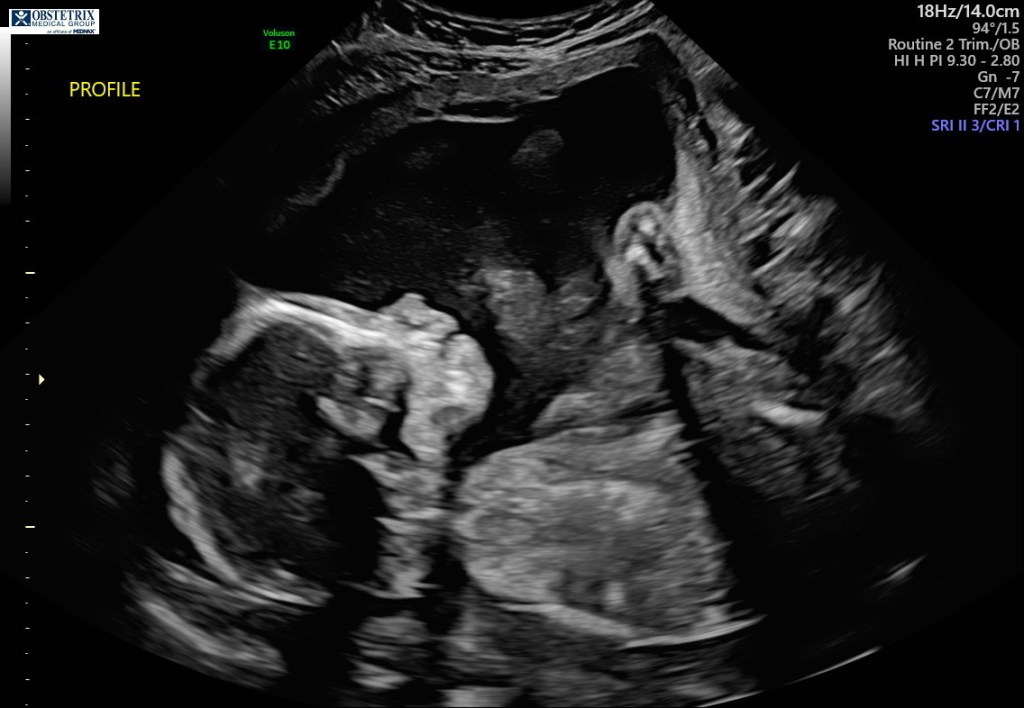

My little sister, Lola, got sick today. She was complaining that her stomach hurt her and about thirty minutes later she threw up. We were all really worried for her and just tried to make her feel better. Luckily, by the end of the night she felt a lot better, but in the moment we were terrified. This virus has everyone on edge and if one of us gets sick, we all freak out, because chances are if one of us gets it, we all get it. I am especially worried for my dad because he has heart disease and if he catches the virus, the odds won’t be in his favor. Nonetheless, we are staying positive and trying to focus on the good things going on in life. At least we are all together and healthy. The other person in my family we are worried about is my older sister, Bella. She is twenty-two and is 7 and a half months pregnant. I will be an aunt in June and I am very excited, but my mom is worried she won’t be able to be in the emergency room with her when she gives birth. My sister’s doctor told her a while ago that if the virus does not lessen, my sister will not be allowed to have anyone in the emergency room with her, not her boyfriend or my mother, just my sister and the doctors. Luckily, a few days ago her doctor okayed her boyfriend being in the delivery room with her, which is better than nothing. My sister claims she is not worried, but she has never really been one to show her emotions. The doctor has also said that if the virus is still like this and hasn’t improved that when the baby is born, there is a possibility that my sister won’t be able to hold him for a while to make sure that the baby is isolated and has no chance of catching the virus. I am not quite sure what this would do, but I understand the concern. Now is a really scary time to be in especially when you are pregnant. I have faith that everything will be okay and that my soon to be nephew, Finley, will be a healthy baby boy. Here is a photo of me and my older sister when we were little. I am on the left and she is on the right.

Lola is feeling a lot better today which is great news. The fear has left my family and I and we are feeling a lot better knowing that the cause of Lola’s sickness was most likely something she ate. I decided to write more on my sister and her pregnancy. This is her very first time being pregnant and while it was not expected, I know she is going to make an incredible mother. My sister is very strong, probably the strongest out of all seven of us kids. She is also incredibly smart and graduated high school a year early, starting college at 17 years old and graduating at 21 years old. She also has an incredible boyfriend who has been right by her side ever since she found out she was pregnant. They are going to be incredible parents and I am so excited to be an aunt. The baby’s name will be Finley Bradbury. My sister has had a few complications during this pregnancy, such as her doctors thinking there could be a chance that she had gestational diabetes, which is a type of diabetes that only happens during pregnancies. There was also concern that something could be wrong with the baby because my sister is really tiny so her belly was not that big. Luckily, both accounts proved to be wrong and the baby is a healthy little boy. My sister is just petite so her bump isn’t huge like other pregnancies. For instance, she is 30 weeks but her baby measures as a 28 week old baby, causing him to be two weeks behind. However the baby is completely healthy. He is simply small because my sister is small. Another thing that makes my sister’s pregnancy different than others is that she hates being pregnant and is ready for her baby to just be out. My sister does have pregnancy cravings. She eats hotdogs, broccoli, and pop tarts every single day. Her ribs are also constantly hurting and when you are pregnant there is the possibility that the baby can break your ribs and the doctor can not fix it until the baby is delivered. As I said before though, my sister is strong and in two months this will all be worth it. Here are some photos of my sister and her little family.